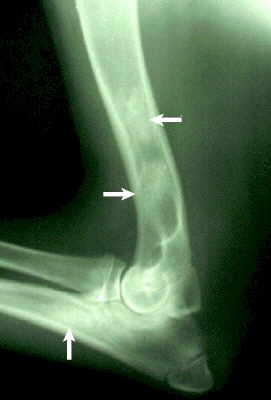

Röntgenbild: rechter Oberarm - Ellbogen - Leonberger, 5 Monate

hochgradige Panostitis mit wolkigen Verschattungen